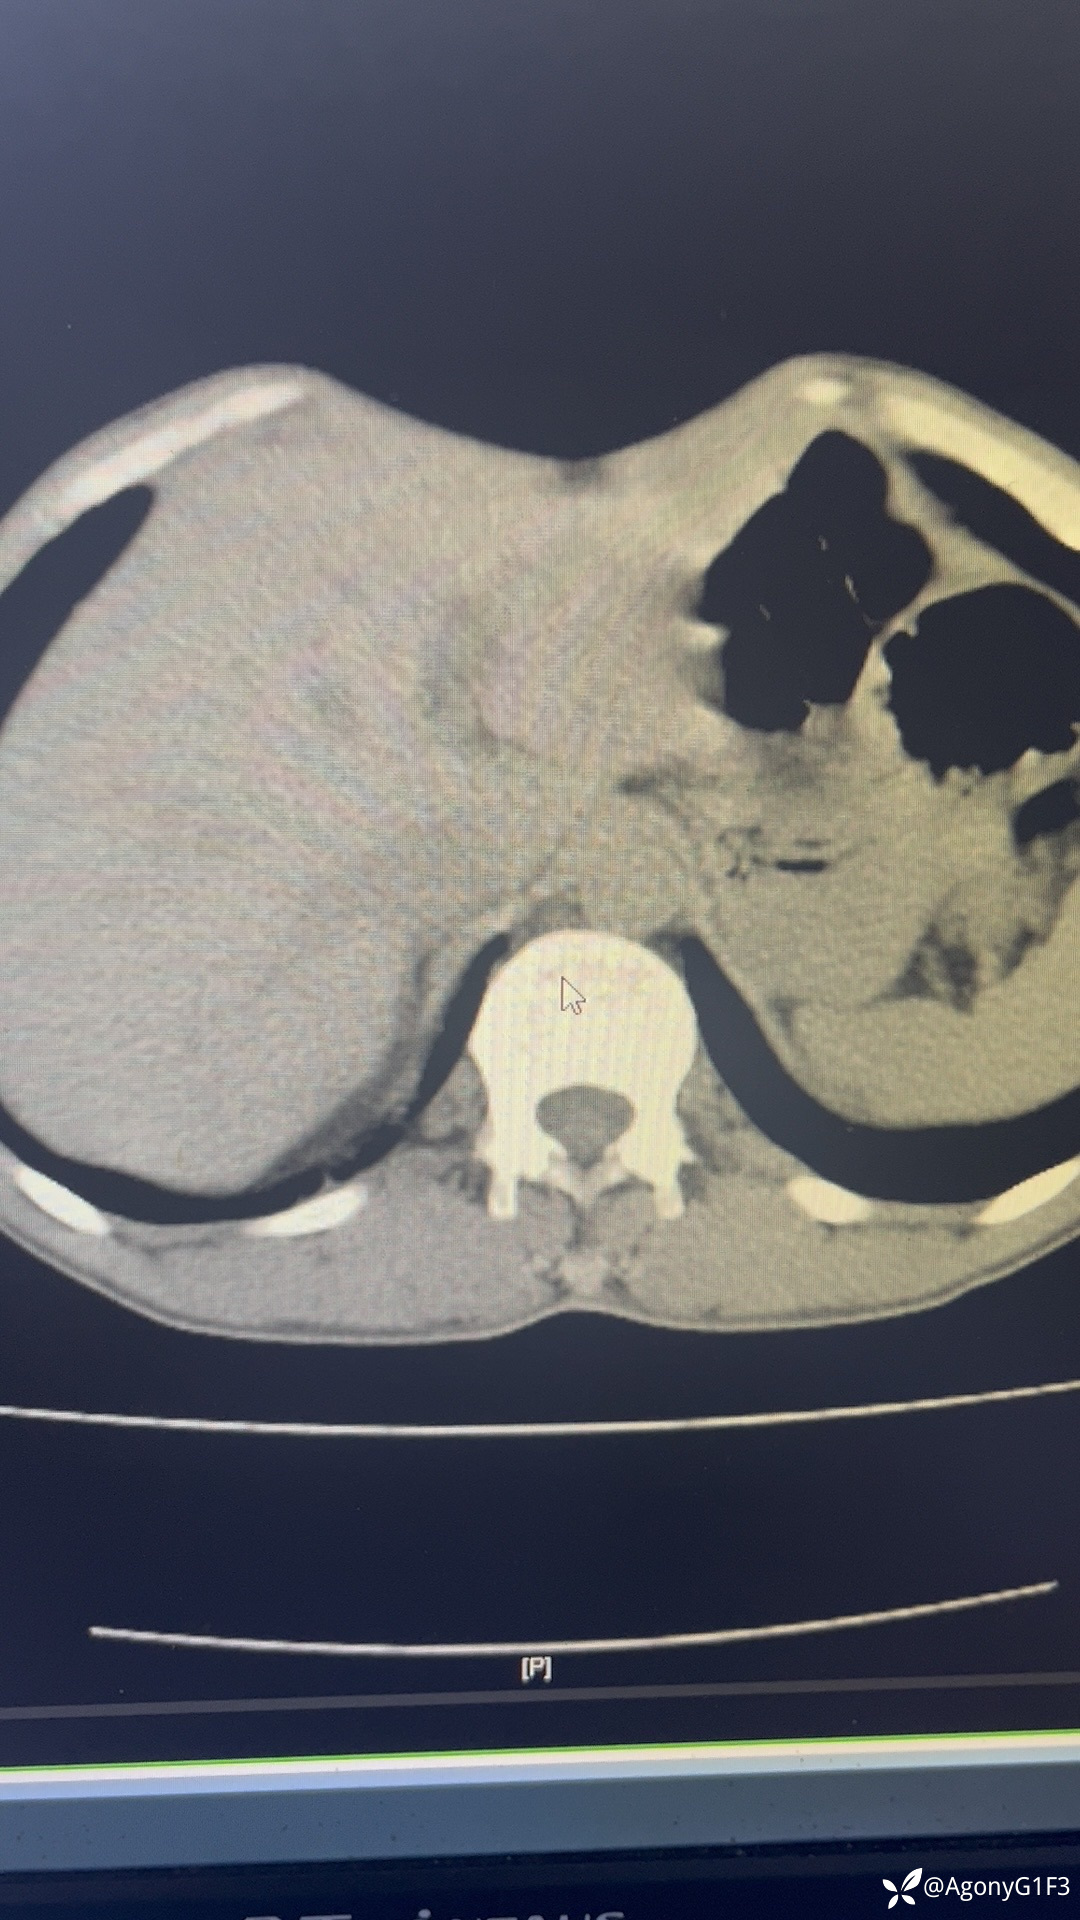

病例间断腹痛一周,Ca199:55,各位大神给看看胰腺有问题吗

普通内科医师 · 发布于 11-11 · 来自 iOS · IP 河北河北